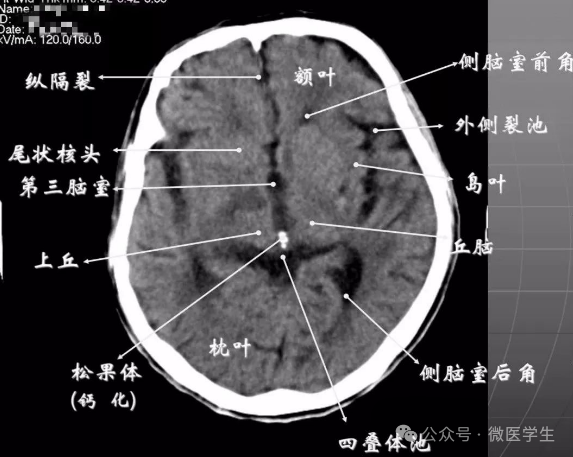

正常解剖

- 鞍上池:在垂体窝上方,位于两侧颅中窝之间,前界为颞叶直回,侧方位颞叶海马,呈五角星形或六角星形。其前角连于纵裂池,两外侧角连于外侧裂池,两后外侧角延续于环池,第六个角位于后缘中间,是角间池。鞍上池边缘为大脑动脉环,池内前部常可见“v”字型视交叉。

显示侧脑室前角的下部:

- 前方—额叶;外侧—尾状核头部;后方中线处—第三脑室,其两侧连接丘脑。

- 基底核、丘脑。

- 内囊前脚(前肢);尾状核和豆状核之间。

- 内囊膝部和后脚(后肢):位于豆状核(由外侧的壳核和内侧的苍白球组成)及丘脑之间。

- 壳核的外侧:外囊、屏状核、最外囊、岛叶(脑岛)。

- 四叠体池:两侧枕叶之间,池内有松果体,向前与第三脑室连接。

基底节(基底核):

- 埋藏在两侧大脑半球深部的灰质核团,是组成锥体外系的主要结构。

- 内囊:位于丘脑、尾状核、豆状核之间的白质区,是由上、下行的传导束密集而成。分为三部分:前肢、膝部、后肢。膝部由皮质脑干束;后肢有皮质脊髓束、丘脑皮质束、听辐射和视辐射。

- 外囊:是位于屏状核和豆状核之间的白质带,主要由岛叶发出的皮质被盖纤维组成。

由额、颞、枕叶构成,两侧侧脑室体部之间为透明隔,外侧为尾状核和体部。侧脑室后角(枕角)可不对称,室内可见脉络丛钙化。中线处可见大脑纵裂池和大脑镰。